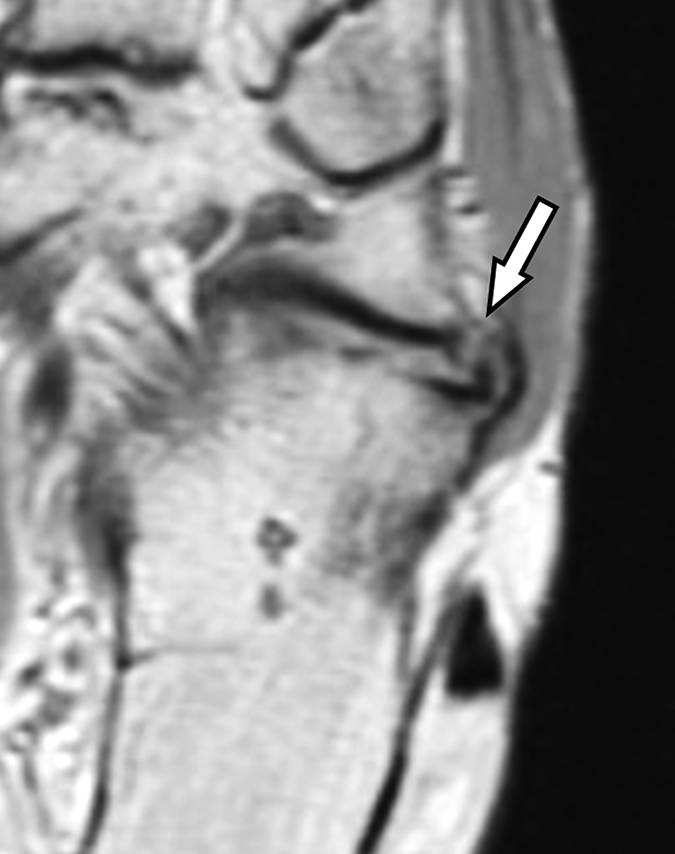

图4A-男,43岁,从马身上掉下来,经历过疼痛,踝关节背部出现瘀伤。A,在损伤后2天获得的X线照片显示了在关节上方约5cm处的跟腱中的骨片(箭头)。

图4B-男,43岁,从马身上掉下来,经历过疼痛,踝关节背部出现瘀伤。B,损伤后6周获得的矢状T1加权MR图像显示加厚的跟腱。 在腱内存在不均匀的信号强度,低信号强度的区域(直箭头)在撕脱位置上方约5cm处, 结节撕脱缺损(弯曲的箭头)